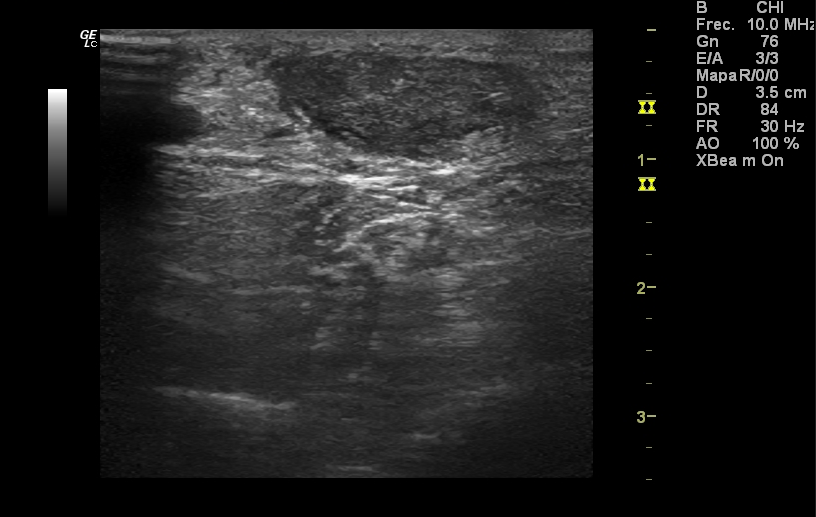

Hombre de 82 años alérgico a betalactámicos, dislipémico, hipertenso y EPOC, que es valorado en Urgencias por un cuadro catarral, tras el cual se ajusta medicación domiciliaria y se pauta levofloxacino 500 mg/día durante 5 días, ante la sospecha de reagudización con criterios de infección sobreañadida.Hallazgos ecográficos

Rotura del espesor completo de ambos tendones Aquíleos, a 4 cm del borde superior del calcáneo aproximadamente, con retracción del cabo proximal y GAP entre ambos cabos de 3 cm. No se ve derrame articular, aunque sí cierto edema de tejido celular subcutáneo.Pruebas complementarias